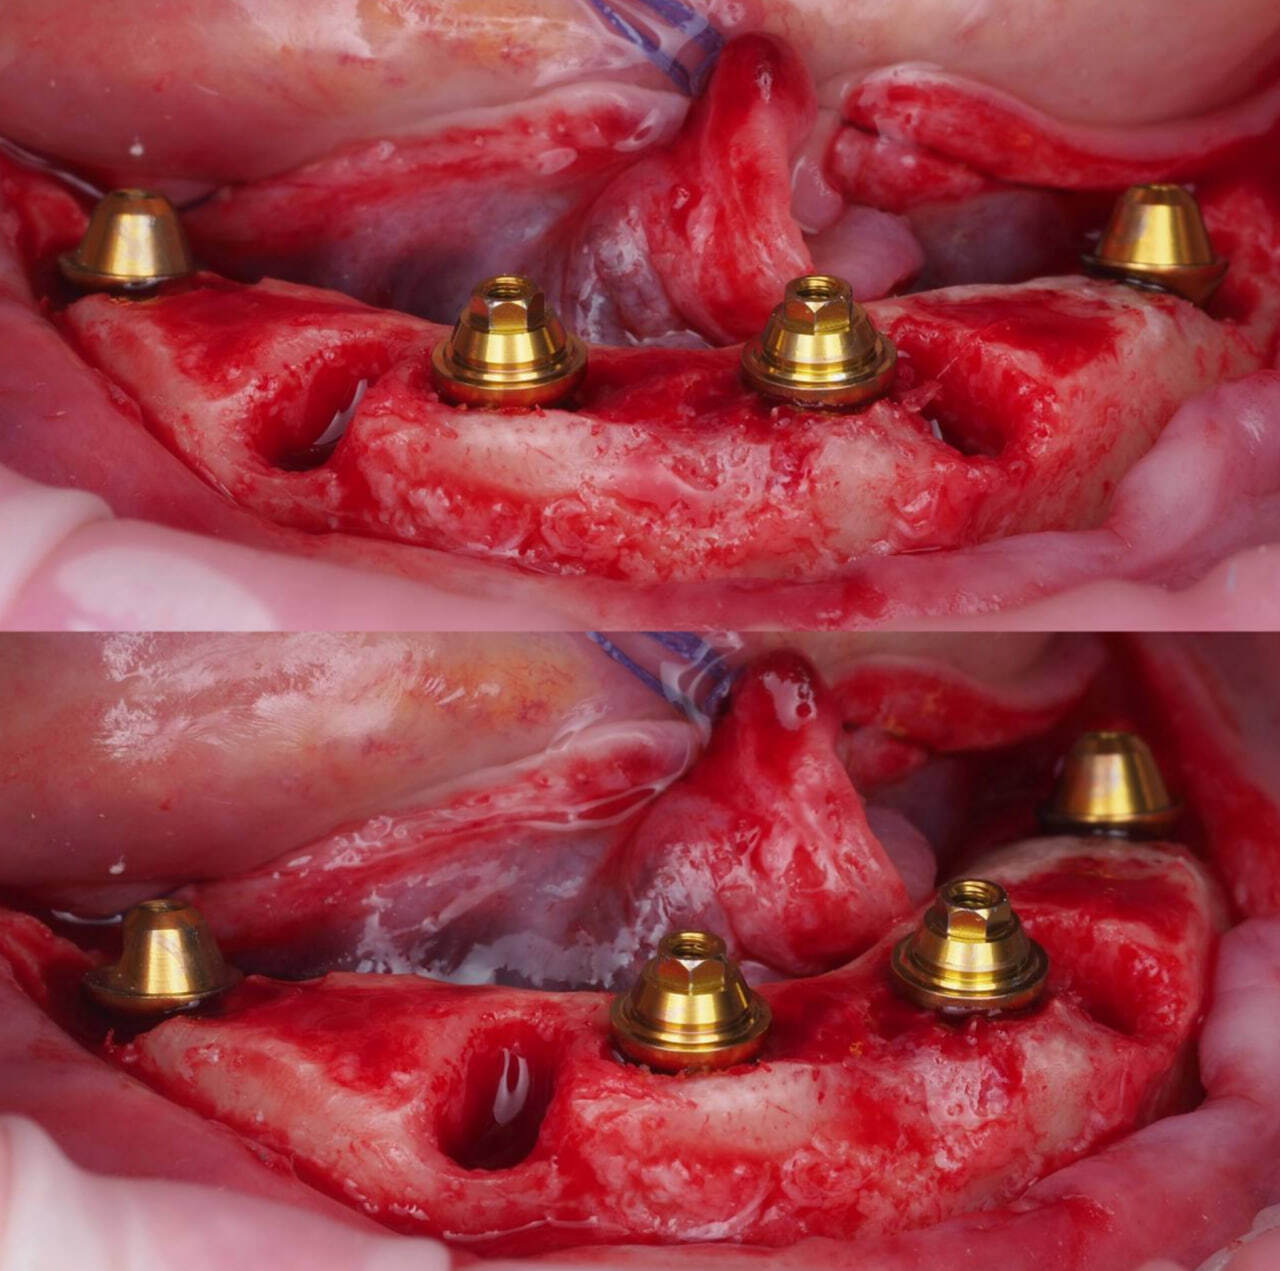

После фиксации временного протеза на верхней челюсти проведена операция на нижней челюсти.

Несостоятельные зубы удалены, проведена редукция костной ткани гребня.

Не смотря на то, что операция проводилась на нижней челюсти, плотность костной ткани была низкая. Было принято решение установить импланты Эниридж с выраженной резьбой для предсказуемой стабилизации.

Установлено 4 имплантата AnyRidge, зафиксированы мультиюниты.